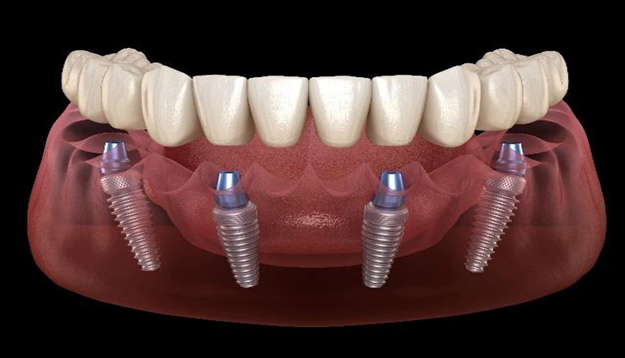

How Much Does All On Four Dental Implant Treatment Cost? Dental implants are the best way to get fixed teeth…

How much Does a Dental Implant Cost for One Tooth? You might have heard about dental implants if you are…

Temporary Eating Habits After Your Dental Implant Treatment Dental implants are one of the best solutions these days for missing…

Full Mouth Dental Implants – Case of the Month at US Dental Clinic in Ahmedabad Patient visited US Dental clinic…